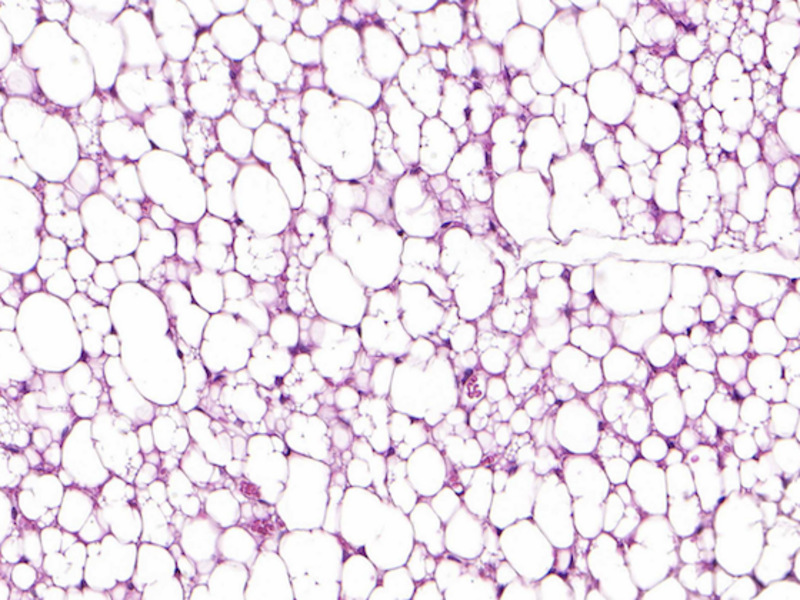

Fettgewebe einer Maus mit weissen und beigen Fettzellen. Die kleineren Zellen mit mehreren Tröpfchen im Innern sind beige Fettzellen (mikroskopische Aufnahme). (Bild: Anand Sharma / ETH Zürich)

Weiss, braun, beige. Das sind die Farben der Fettzellen. Weisse Fettzellen speichern in unserem Körper Fett als Energiereserve. Wir brauchen diese Zellen. Zu viele davon wollen wir aber aus gesundheitlichen Gründen nicht. Die braunen Fettzellen sind vor allem bei Säuglingen aktiv. Sie produzieren Wärme und halten damit die Körpertemperatur der Babys aufrecht. Braunes Fettgewebe nimmt jedoch im Lauf des Lebens ab; Erwachsene haben nur noch sehr wenig davon. Beige Fettzellen schliesslich können ebenfalls Wärme produzieren, wenn auch etwas weniger gut als braune Fettzellen. Sie kommen auch bei Erwachsenen vor – eingestreut ins weisse Fettgewebe, vor allem im Nacken- und Schulterbereich. Sie helfen mit, überschüssige Energie zu verbrauchen.